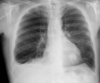

11

Pneumothorax